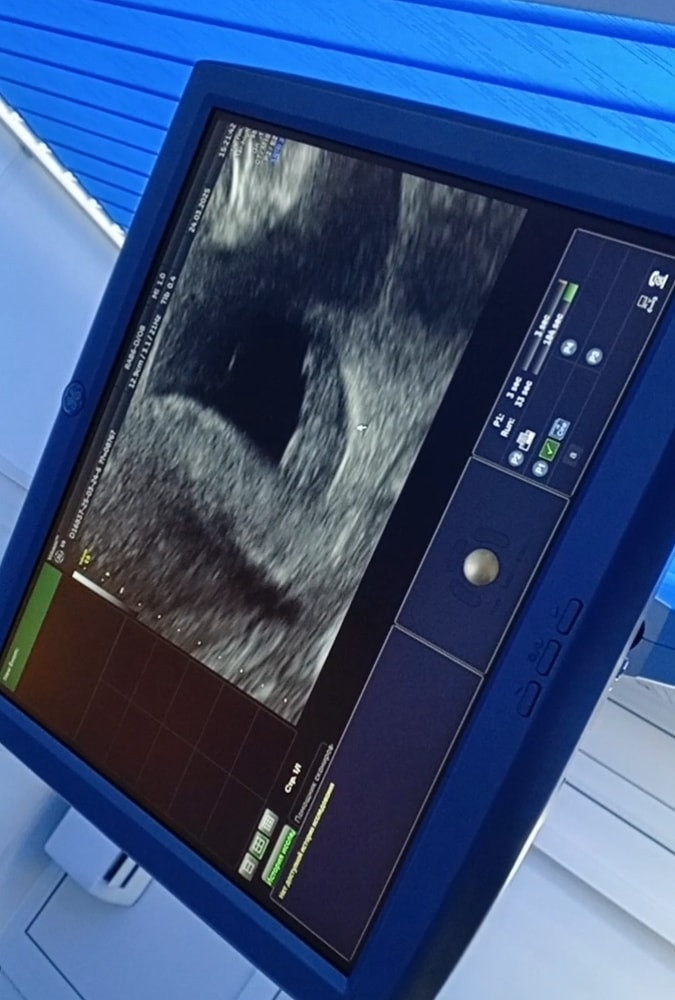

9 недель

Вчера была на узи. Ровно 9 недель беременности) сердечко 175 ударов в минуту)

Мы очень тебя ждём, наше счастье💕